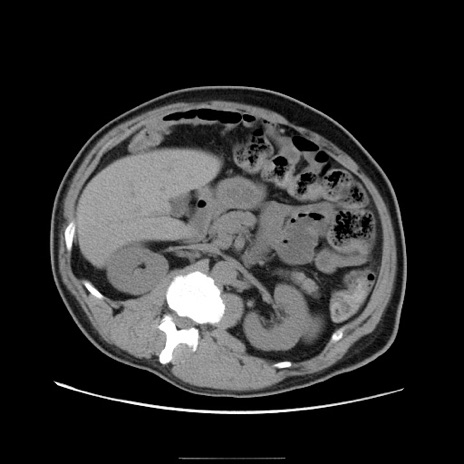

冠状断像

【症例】50歳代男性

【主訴】腹痛

【現病歴】AVMからの被殻出血のため回復期リハ病棟入院中。 本日午後3時頃急に下腹部痛が出現した。

【既往歴】AVM、被殻出血、虫垂炎、高血圧

【身体所見】意識晴明、左半身不全麻痺、会話の理解は良好、36.5°C、腹部:膨隆、全体に板状硬、下腹部正中に圧痛点あり、反跳痛-、筋性防御不明、右下腹部にope scar

【データ】WBC 9400、CRP 0.06